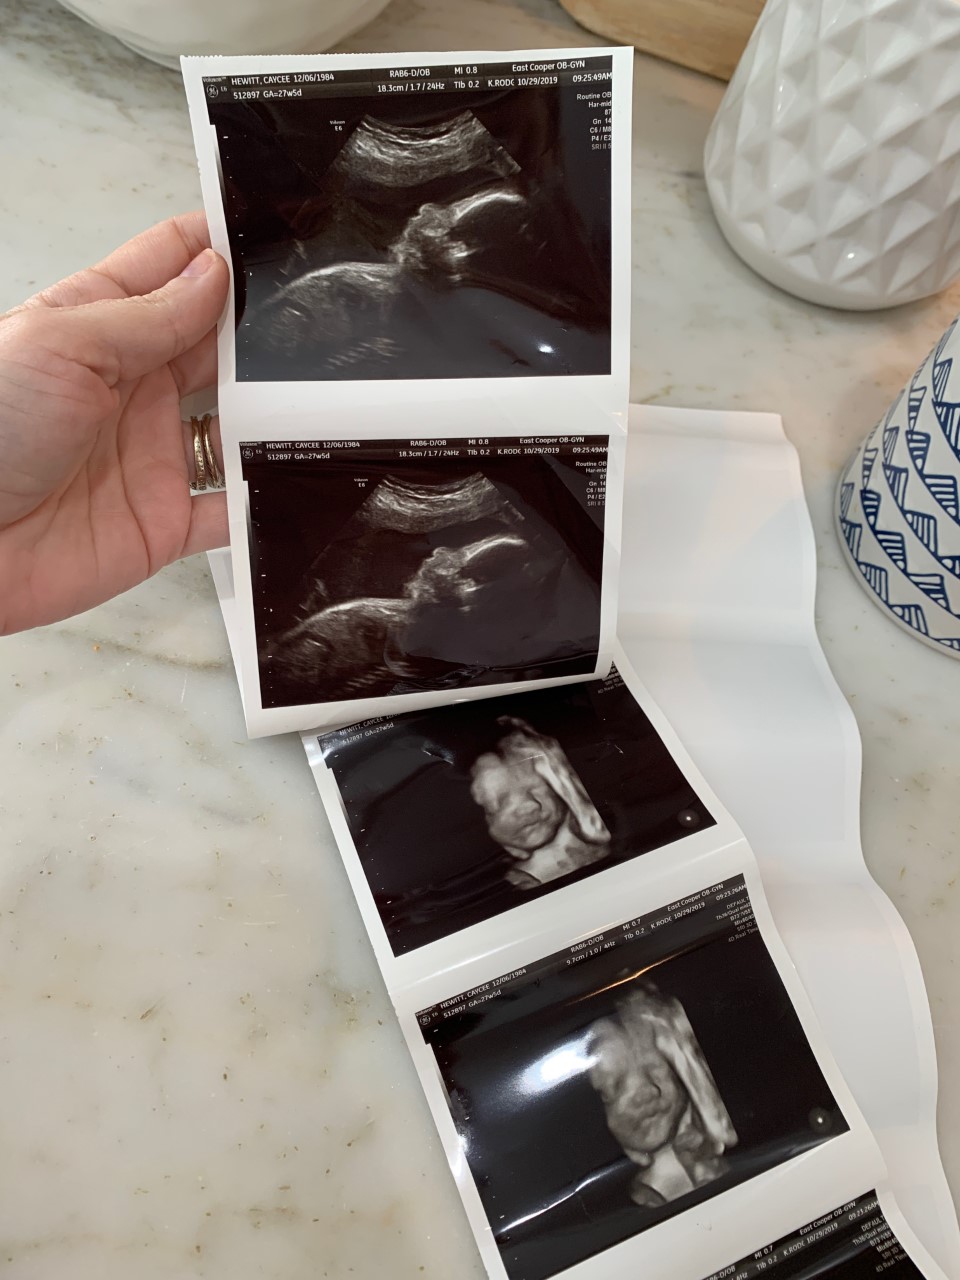

We had another ultrasound this week and it was so exciting to get to see our sweet baby girl in my belly. Todd and I are both very excited and so ready for January!!

FOUR //

Speaking of being ready for January, at our appointment we had to make a game plan for her birth. As most of you know, I had to have a c-section with both Carson and Taylor, but this time I’ve been given the go-ahead to try and attempt a v-back. At this point, my percentage is looking pretty good for it being a success, but we really won’t know anything for sure until right before her due date. That being said, if any of you are comfortable sharing, I would LOVE to hear from any of you that have had a successful (or unsuccessful) v-back and what your experience was like.